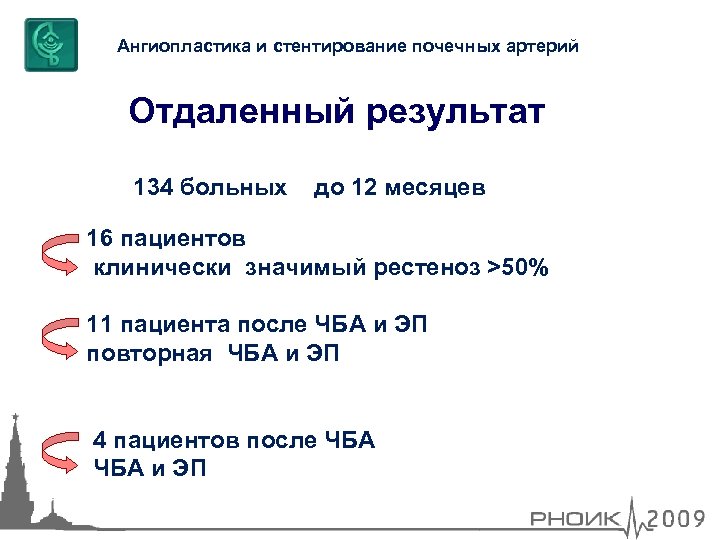

Ангиопластика и стентирование почечных артерий Отдаленный результат 134 больных до 12 месяцев 16 пациентов клинически значимый рестеноз >50% 11 пациента после ЧБА и ЭП повторная ЧБА и ЭП 4 пациентов после ЧБА и ЭП

Ангиопластика и стентирование почечных артерий Отдаленный результат 134 больных до 12 месяцев 16 пациентов клинически значимый рестеноз >50% 11 пациента после ЧБА и ЭП повторная ЧБА и ЭП 4 пациентов после ЧБА и ЭП